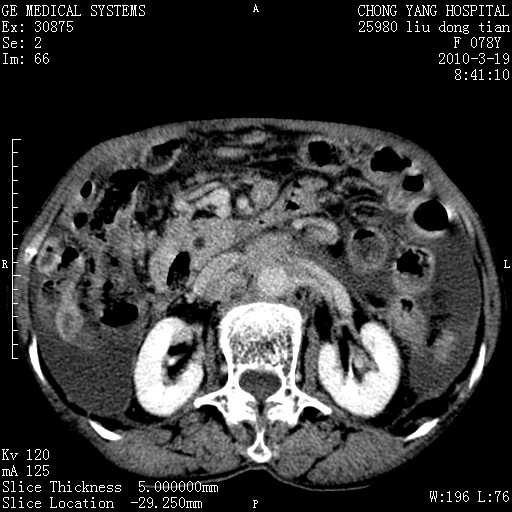

标题: CT25199:F 78Y 腹胀半年 消瘦乏力 [打印本页]

胆囊壁增厚并明显强化,胆囊癌伴多发转移瘤可能性大,淋巴瘤不除外,右肾囊肿,胸腹水.

考虑nhl,肝、脾、腹膜腔及腹膜后多发淋巴结受侵,腹水,右肾囊肿,慢性胆囊炎,右侧少量胸腔积液。

首先考虑恶性淋巴瘤 。

胰头有肿块形成,胰头ca伴肝脾、腹膜腹膜后转移

胆囊有软组织影有强化,支持胆囊癌,肝脾、腹膜后淋巴结转移。

nhl的淋巴结多围绕主动脉,而且主动脉会移位,所以不考虑nhl。

分开来讲:肝左叶、尾叶病灶有不均强化像肝癌;

脾脏病灶无强化,像多发囊肿或淋巴管瘤,不除外淋巴瘤(低强化);

胆囊增生性病变:胆囊癌,腺肌增生症,慢性胆囊炎;

肝门、胰腺头、腹膜后多个团块: 淋巴瘤,转移;

腔静脉肝内段细小有无布加可能?

一元论最好了 淋巴瘤所致改变; 胆囊癌转移不像,胆囊周围肝组织清晰,肝癌淋巴结转移?三元论都不止。

胰头ca伴肝脾、腹膜腹膜后转移!

最后报的胰头癌多发转移,脾脏单独考虑囊肿或淋巴管瘤。